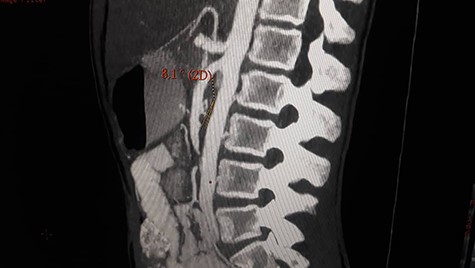

Patient underwent contrast enhanced CT scan for abdomen and pelvis, which revealed severely dilated stomach and significant dilatation of the duodenum up to the level of the distal third part, abrupt narrowing (transition zone) was seen just anterior to the AA and posterior to the SMA (Figs. 1 and 2) as well as significant reduction of the aortomesenteric angle (measuring 8.1°) and aortomesenteric distance measuring about 7 mm (Fig. 1).

Contrast enhanced CT scan abdomen and pelvis (sagittal view) showing significant reduction of the aortomesenteric angle (measuring 8.1°) and aortomesenteric distance measuring about 7 mm.